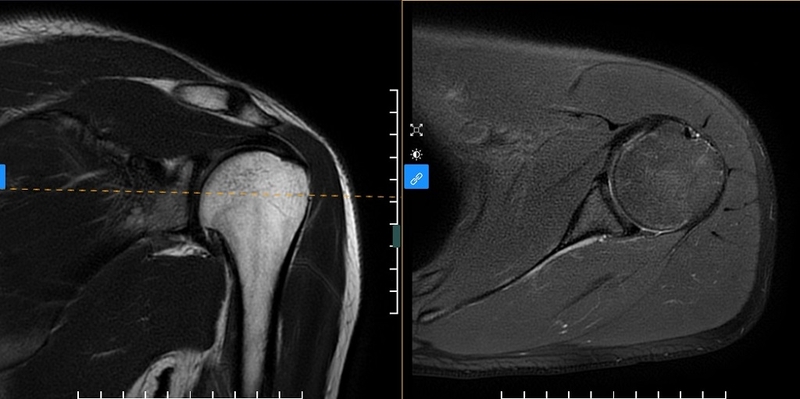

Hình ảnh từ kỹ thuật chụp MRI khớp vai nổi bật với độ tương phản cao và khả năng hiển thị chi tiết giải phẫu cơ thể, giúp phát hiện tổn thương hình thái và cấu trúc bên trong một cách chính xác.

Khả năng tái tạo hình ảnh ba chiều và không gây tác động phụ khiến nó trở nên ngày càng phổ biến trong nhiều lĩnh vực chuyên môn khác nhau. Trong số đó, nó có vai trò quan trọng trong việc chẩn đoán và điều trị nhiều bệnh lý liên quan đến hệ thống cơ bản xương khớp.